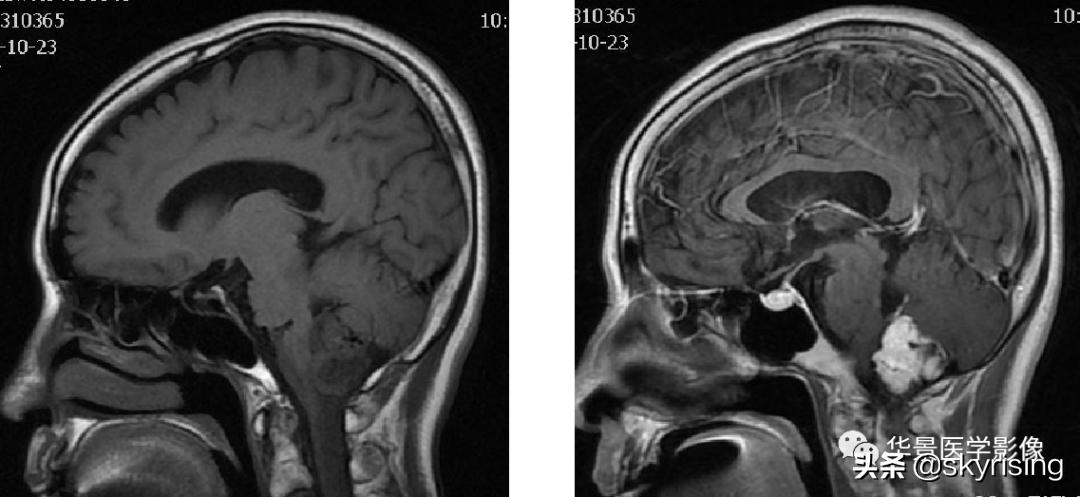

以下依次为T2WI、FLAIR、T1WI、增强、DWI及ADC:

上图白色箭头:小脑延髓池内延髓背侧不规则形团块影,小脑半球、延髓、第四脑室受压变形,所见诸脑室未见增宽。

蓝色箭头:延髓受压前后径变窄,T1信号减低,考虑合并水肿。

黄色箭头:病灶边缘见流空信号血管影。

小脑延髓池内见不规则异常信号影,呈长T1长T2信号,内部信号不均,边缘见稍粗大流空信号血管影,FLAIR少许片状低信号,增强呈明显强化,DWI不均质低信号,ADC不均质高信号。小脑半球、延髓、第四脑室受压变形。临近延髓变窄,呈长T1长T2信号。